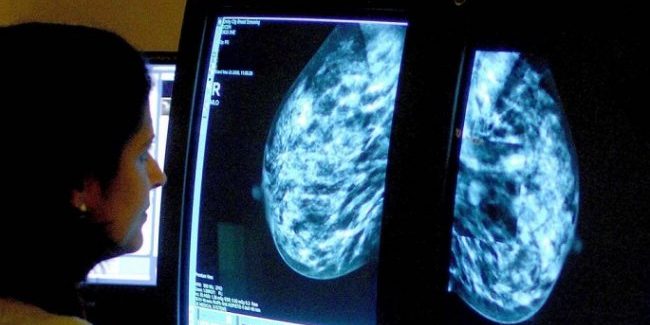

Маммографическое обследование женщин в возрасте 40-49 лет, возможно, ежегодно спасает до 400 жизней, пришли к выводу ученые Лондонского университета королевы Марии.

В работе, которая была опубликована на страницах журнала Lancet Oncology, медики пришли к выводу, что обследование женщин в возрасте от 40 до 49 лет, сокращает количество летальных исходов от рака на четверть за первые 10 лет.

Отмечается, что в этой возрастной группе из 53 883 женщин 83 скончались от рака.

Для сравнения ученые проанализировали данные женщин в возрасте от 50 лет и старше. Оказалось, что из 106 953 женщин этой группы от рака скончались 219 человек, пишет Independent.

В результате ученые пришли к выводу, что обследование в сравнительно более раннем возрасте значительно сокращает число летальных исходов.